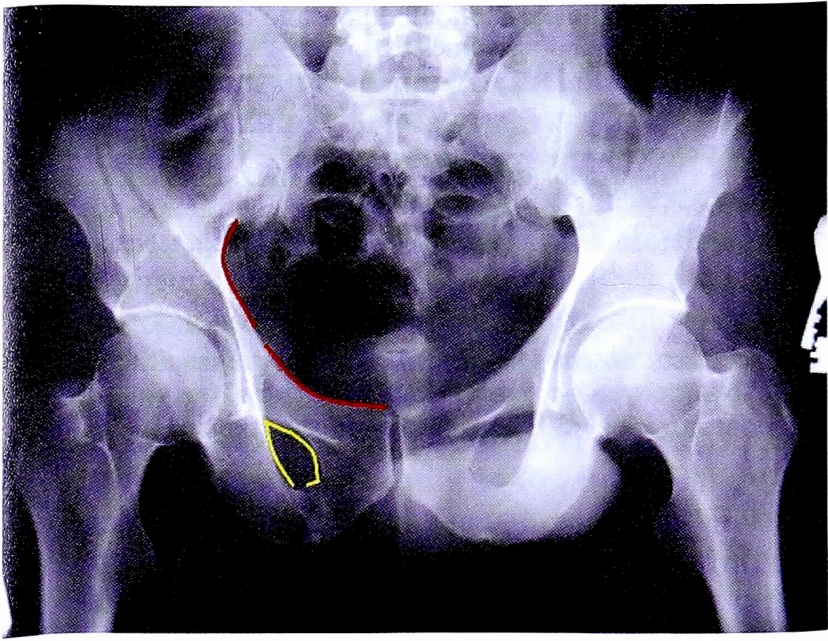

На обзорной рентгенограмме, представленной на рис. 14 достоверно определяется нарушение непрерывности подвздошно-гребешковой и подвздошно-седалищной линии.

Рис. 14. Обзорная рентгенография таза пациента с переломом вертлужной впадины.

Fig. 14. АР pelvic X-ray of patient with acetabular fracture.

С помощью рентгенограммы в косой запирательной проекции, выполненной по методике НМИЦ ТО, диагностирован перелом задней стенки со смещением отдельного фрагмента. Также с помощью прицельного снимка определена целостность контуров запирательного отверстия (рис. 15).

Рис. 15. Рентгенография правого тазобедренного сустава в косой-запирательной проекции, выполнена по методике НМИЦ ТО. Стрелками показан перелом и отдельный фрагмент задней стенки.

Fig. 15. Obturator oblique view made with CITO method. Arrows shows separated posterior wall fragment.